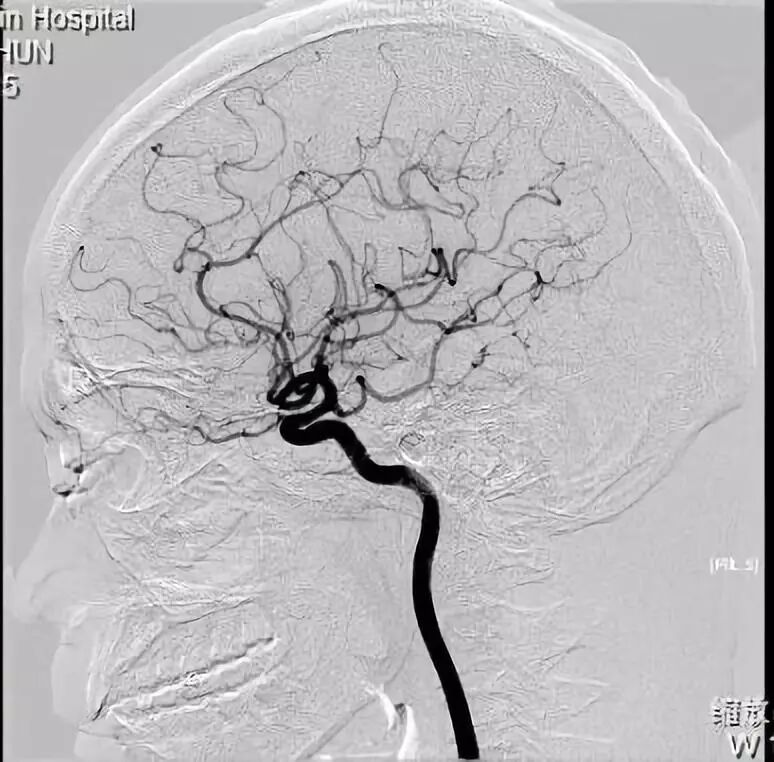

椎动脉侧位造影,右侧大脑后动脉p1段正常存在

魏继光,男,55,左侧大脑后p1段动脉瘤